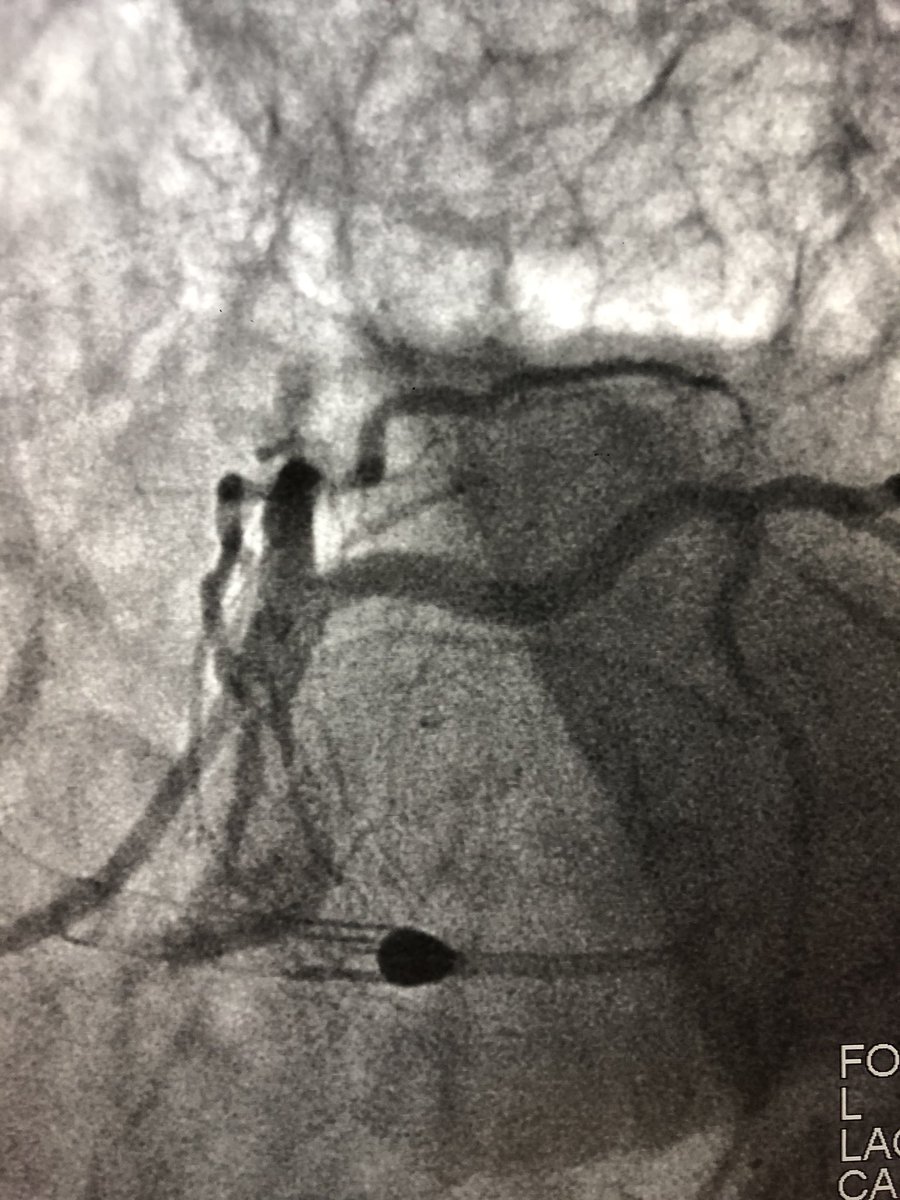

72 y/o WM with AS and LM/MV CAD. Complex bilateral iliac disease. #PercAx for Impella CP. Right ulnar access for DK crush for LM disease with left #radialfirst access for management of left axillary artery. Big thanks to @DrAmirKaki for showing me how.

matheenkhuddus's tweet image. 72 y/o WM with AS and LM/MV CAD. Complex bilateral iliac disease. #PercAx for Impella CP. Right ulnar access for DK crush for LM disease with left #radialfirst access for management of left axillary artery. Big thanks to @DrAmirKaki for showing me how.